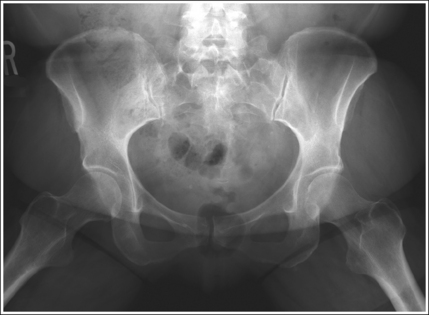

See Figure 7-26 and Box 7-6.

The pelvis demonstrates an AP projection. The ischial spines are aligned with the pelvic brim, the sacrum and coccyx are aligned with the symphysis pubis, and the ilia and obturator foramina are open and uniform in size and shape.

• An AP projection of the pelvis is accomplished by placing the patient on the imaging table with the legs flexed and abducted (Figure 7-27). To ensure that the pelvis is not rotated, judge the distance from the ASIS to the imaging table on each side. The distances should be equal.

• Detecting pelvic rotation. A nonrotated AP oblique pelvis projection will demonstrate symmetrical ilia and obturator foramina. Rotation can be detected by evaluating the relationships of the ischial spines with the pelvic brim and of the sacrum and coccyx with the symphysis pubis. The ischial spines should be aligned with the pelvic brim and the sacrum and coccyx should align with the symphysis pubis on a nonrotated pelvis. If the pelvis is rotated into an LPO position, the left ilium is wider than the right, the left obturator foramen is narrower than the right, the left ischial spine is demonstrated without pelvic brim superimposition, and the sacrum and coccyx are not aligned with the symphysis pubis but are rotated toward the right hip (see Image 19). If the patient is rotated into an RPO position, the opposite is true. The right ilium is wider than the left, the right obturator foramen is narrower than the left, the right ischial spine is demonstrated without pelvic brim superimposition, and the sacrum and coccyx are rotated toward the left hip.

IMAGE 19

The lesser trochanters are in profile medially, and the femoral necks are superimposed over the adjacent greater trochanters.

• Accurate femur positioning. To position the greater trochanters beneath the proximal femurs accurately and position the lesser trochanters in profile, flex the patient's knees and hips until the femurs are angled 60 to 70 degrees with the imaging table (20 to 30 degrees from vertical; Figure 7-28).

• Poor distal femur elevation. For an AP oblique pelvis projection, the relationship of the greater and the lesser trochanters with the proximal femurs is determined when the patient flexes the knees and hips. If the knees and hips are not flexed enough to place the femur at a 60- to 70-degree angle with the imaging table, the greater trochanters are demonstrated laterally, as with an AP projection (see Image 20). If the knees and hips are flexed too much, placing the femurs at an angle greater than 60 to 70 degrees with the imaging table, the greater trochanters are demonstrated medially Image 9).

IMAGE 20

The femoral necks are partially foreshortened. The proximal aspects of the greater trochanters are demonstrated at a transverse level halfway between the femoral heads and lesser trochanters.

• Accurate leg positioning. To demonstrate the femoral necks and proximal femora with only partial foreshortening and the greater trochanters at a transverse level halfway between the femoral heads and lesser trochanters on an AP oblique pelvis projection, abduct the femoral shafts to a 45-degree angle from vertical (Figures 7-26 and 7-29).

• Effect of leg abduction. The degree of femoral abduction determines the amount of femoral neck foreshortening and the transverse level at which the greater trochanters are demonstrated between the femoral heads and lesser trochanters.

• Poor leg abduction. If the femoral shafts are abducted to 20 to 30 degrees from vertical (60- to 70-degree angle from the imaging table; Figure 7-30), the femoral necks are demonstrated without foreshortening and the proximal greater trochanters are at the same transverse level as the lesser trochanters on an AP oblique pelvis projection (see Image 21). If the femoral shafts are abducted until they are placed next to the imaging table (Figure 7-31), the proximal femoral shafts are demonstrated without foreshortening, the proximal greater trochanters are at the same transverse level as the femoral heads, and the femoral necks are demonstrated on end on an AP oblique pelvis projection (see Image 22).

IMAGE 21

IMAGE 22

• Importance of symmetrical femoral abduction. An AP oblique pelvis projection may not demonstrate the proximal femurs with exactly the same degree of femoral abduction. How each proximal femur appears depends on the degree of femoral abduction placed on that leg. As a standard, unless the AP oblique pelvis projection is ordered to evaluate hip mobility, both femurs should be abducted equally for the image. This symmetrical abduction helps prevent pelvic rotation. It may be necessary to position an angled sponge beneath the patient's femurs to maintain the desired femoral abduction.

The left obturator foramen is narrower than the right foramen, the left ischial spine is demonstrated without pelvic brim superimposition, and the sacrum and coccyx are rotated toward the right hip. The patient was rotated onto the left hip (LPO).

Rotate the patient toward the right hip until the ASISs are positioned at equal distances from the imaging table.

The greater trochanters are partially demonstrated laterally, indicating that the leg was flexed less than the needed 60 to 70 degrees from the imaging table.

Increase the degree of knee and hip flexion until the femurs are positioned at a 60- to 70-degree angle with the imaging table.

The femoral necks are demonstrated without foreshortening, and the proximal greater trochanter and lesser trochanter are demonstrated at approximately the same transverse level. The patient's femurs were in only slight abduction, at approximately a 70-degree angle with the imaging table (20 degrees from vertical), as shown in Figure 7-30.

Consult with reviewers in your facility to determine whether this is an acceptable image. If the proximal femoral shafts demonstrate too much foreshortening, have the patient abduct the femurs to a 45-degree angle with the imaging table.

The femoral necks are demonstrated on end. The proximal greater trochanters are demonstrated on the same transverse level as the femoral heads. The patient's femurs were positioned next to the imaging table, as shown in Figure 7-31.